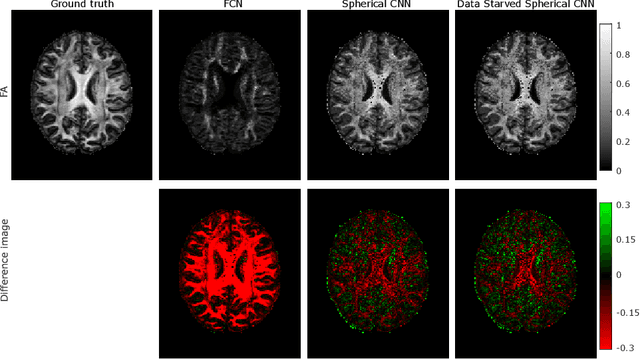

Abstract:This paper demonstrates spherical convolutional neural networks (S-CNN) offer distinct advantages over conventional fully-connected networks (FCN) at estimating scalar parameters of tissue microstructure from diffusion MRI (dMRI). Such microstructure parameters are valuable for identifying pathology and quantifying its extent. However, current clinical practice commonly acquires dMRI data consisting of only 6 diffusion weighted images (DWIs), limiting the accuracy and precision of estimated microstructure indices. Machine learning (ML) has been proposed to address this challenge. However, existing ML-based methods are not robust to differing dMRI gradient sampling schemes, nor are they rotation equivariant. Lack of robustness to sampling schemes requires a new network to be trained for each scheme, complicating the analysis of data from multiple sources. A possible consequence of the lack of rotational equivariance is that the training dataset must contain a diverse range of microstucture orientations. Here, we show spherical CNNs represent a compelling alternative that is robust to new sampling schemes as well as offering rotational equivariance. We show the latter can be leveraged to decrease the number of training datapoints required.